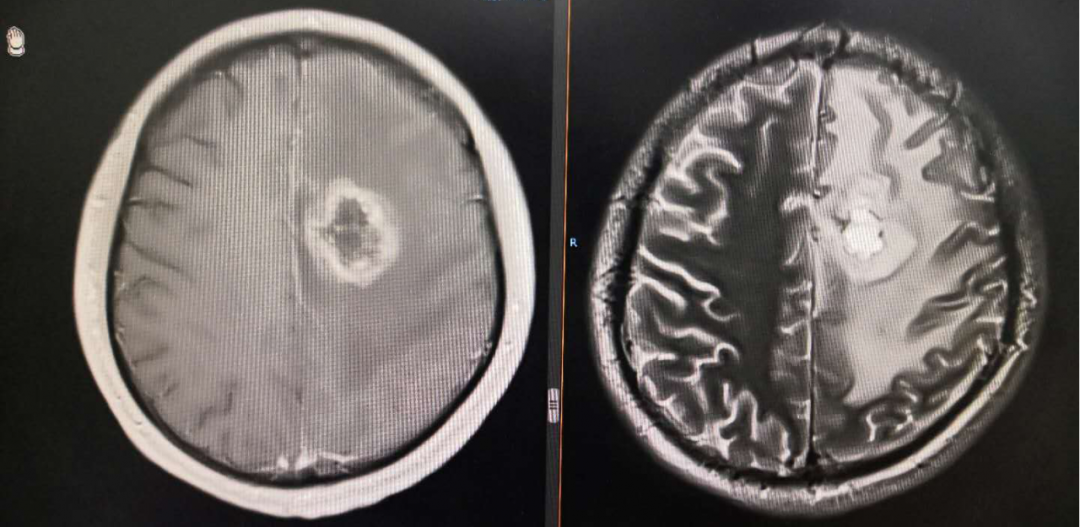

8月份复查再次显示肿瘤进展,由于没有更好的治疗方案,所以暂时继续原方案治疗。

从影像学看该患者是弥漫星形细胞瘤WHO II级,但该患者DWI上呈稍高信号,增强扫描却未见强化,而肿瘤的强化与其级别并非完全成正比,因此推测该病例具有胶质母细胞瘤的特点,WHO分级等同于 IV级。